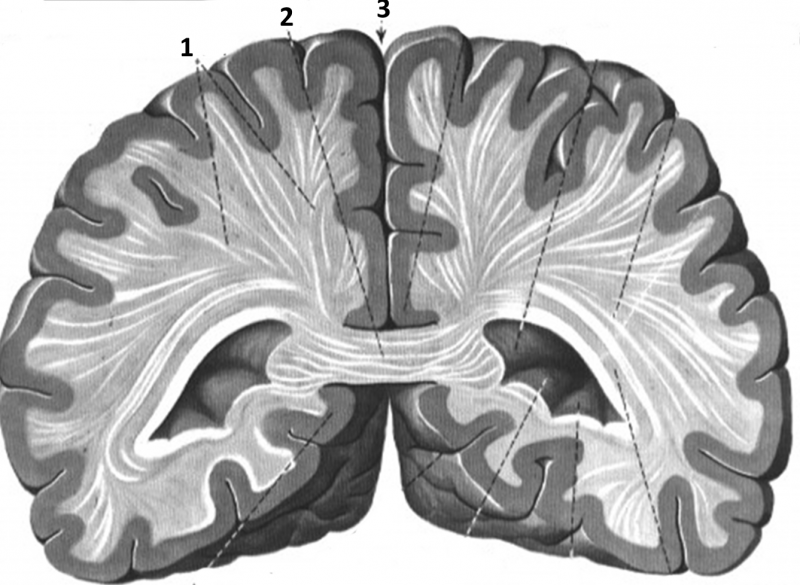

РОЗПІЗНАЙТЕ ОРГАНИ У ФРОНТАЛЬНІЙ ПЛОЩИНІ.

варіанти відповідей